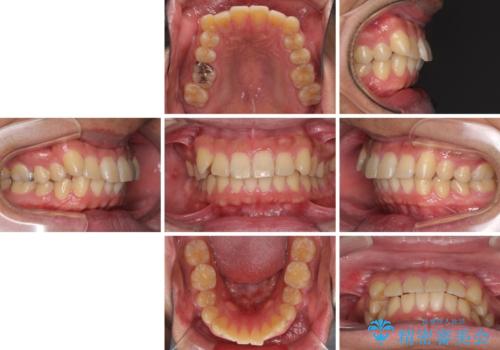

- 20代男性

- インビザライン

- 4年8ヶ月

- 前歯のデコボコを気にして来院された患者様です。

当院でインビザライン矯正治療をされている方からのご紹介ということで、インビザラインでの矯正治療をご希望でした。

ワイヤー矯正に比べ来院頻度は低いものの、新幹線での通院のため、やや治療期間が延びることが懸念されました。

配属異動や長時間勤務などによりインビザラインが十分に装着できない期間があり、インビザライン有効期限5年間ギリギリとなってしまいました。